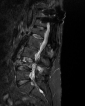

Temmuz 2023Eski lomber stabilizasyon sistemi altında kırık